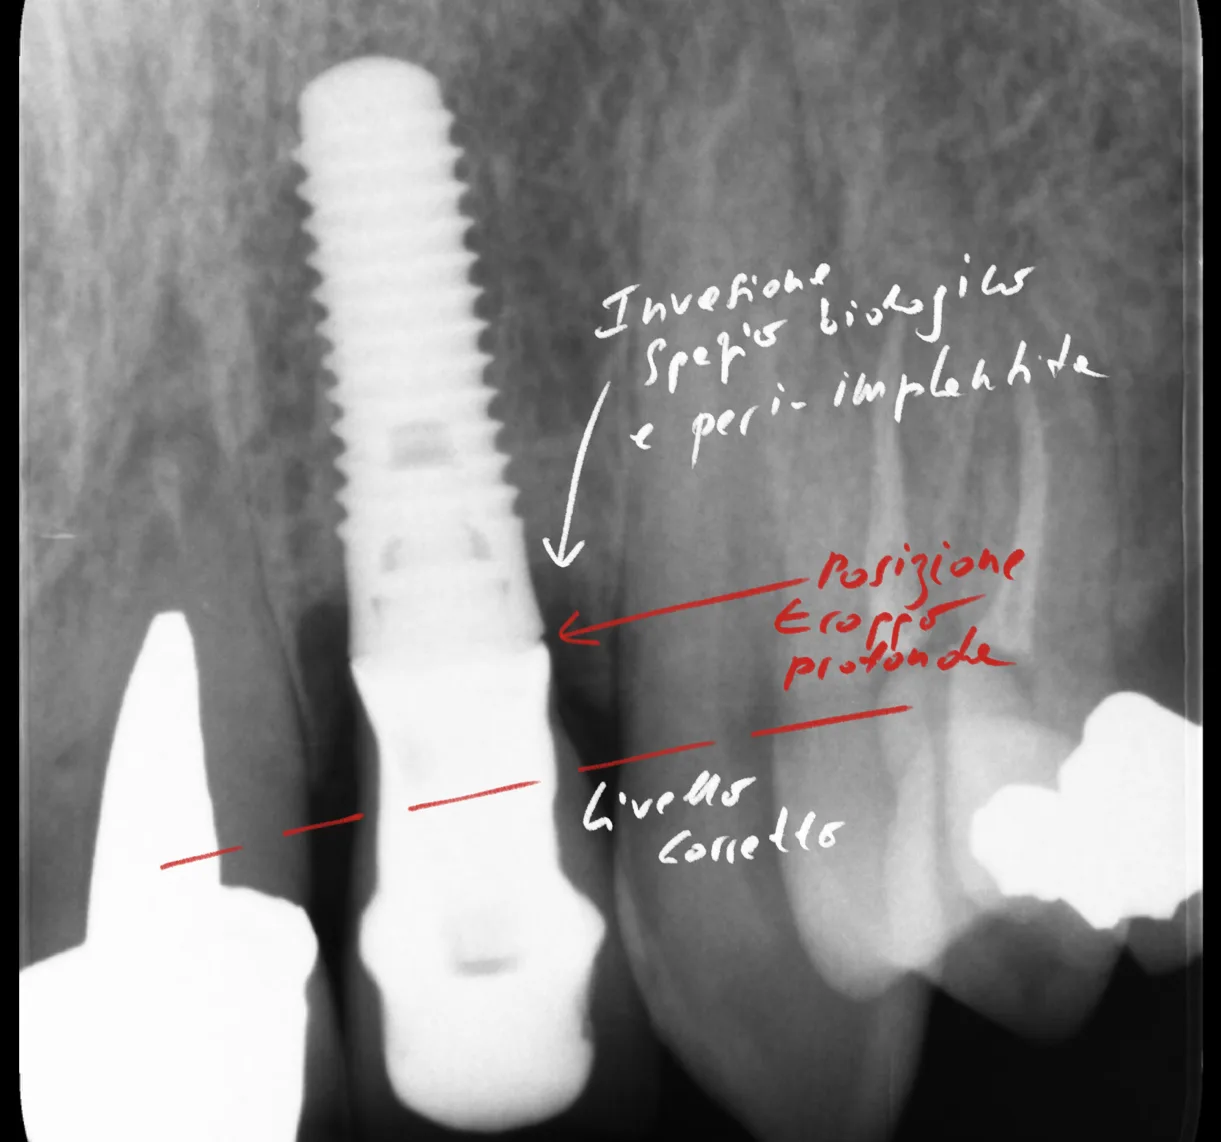

Implantologia

Impianti dentali, carico immediato, GBR, rialzo del seno mascellare

Cresta atrofica in zona 4.6 con difetto osteo-mucoso e cheratinizzata quasi assente: Bonebending 4.0 e impianto in unica seduta. Risultato a 3 mesi.